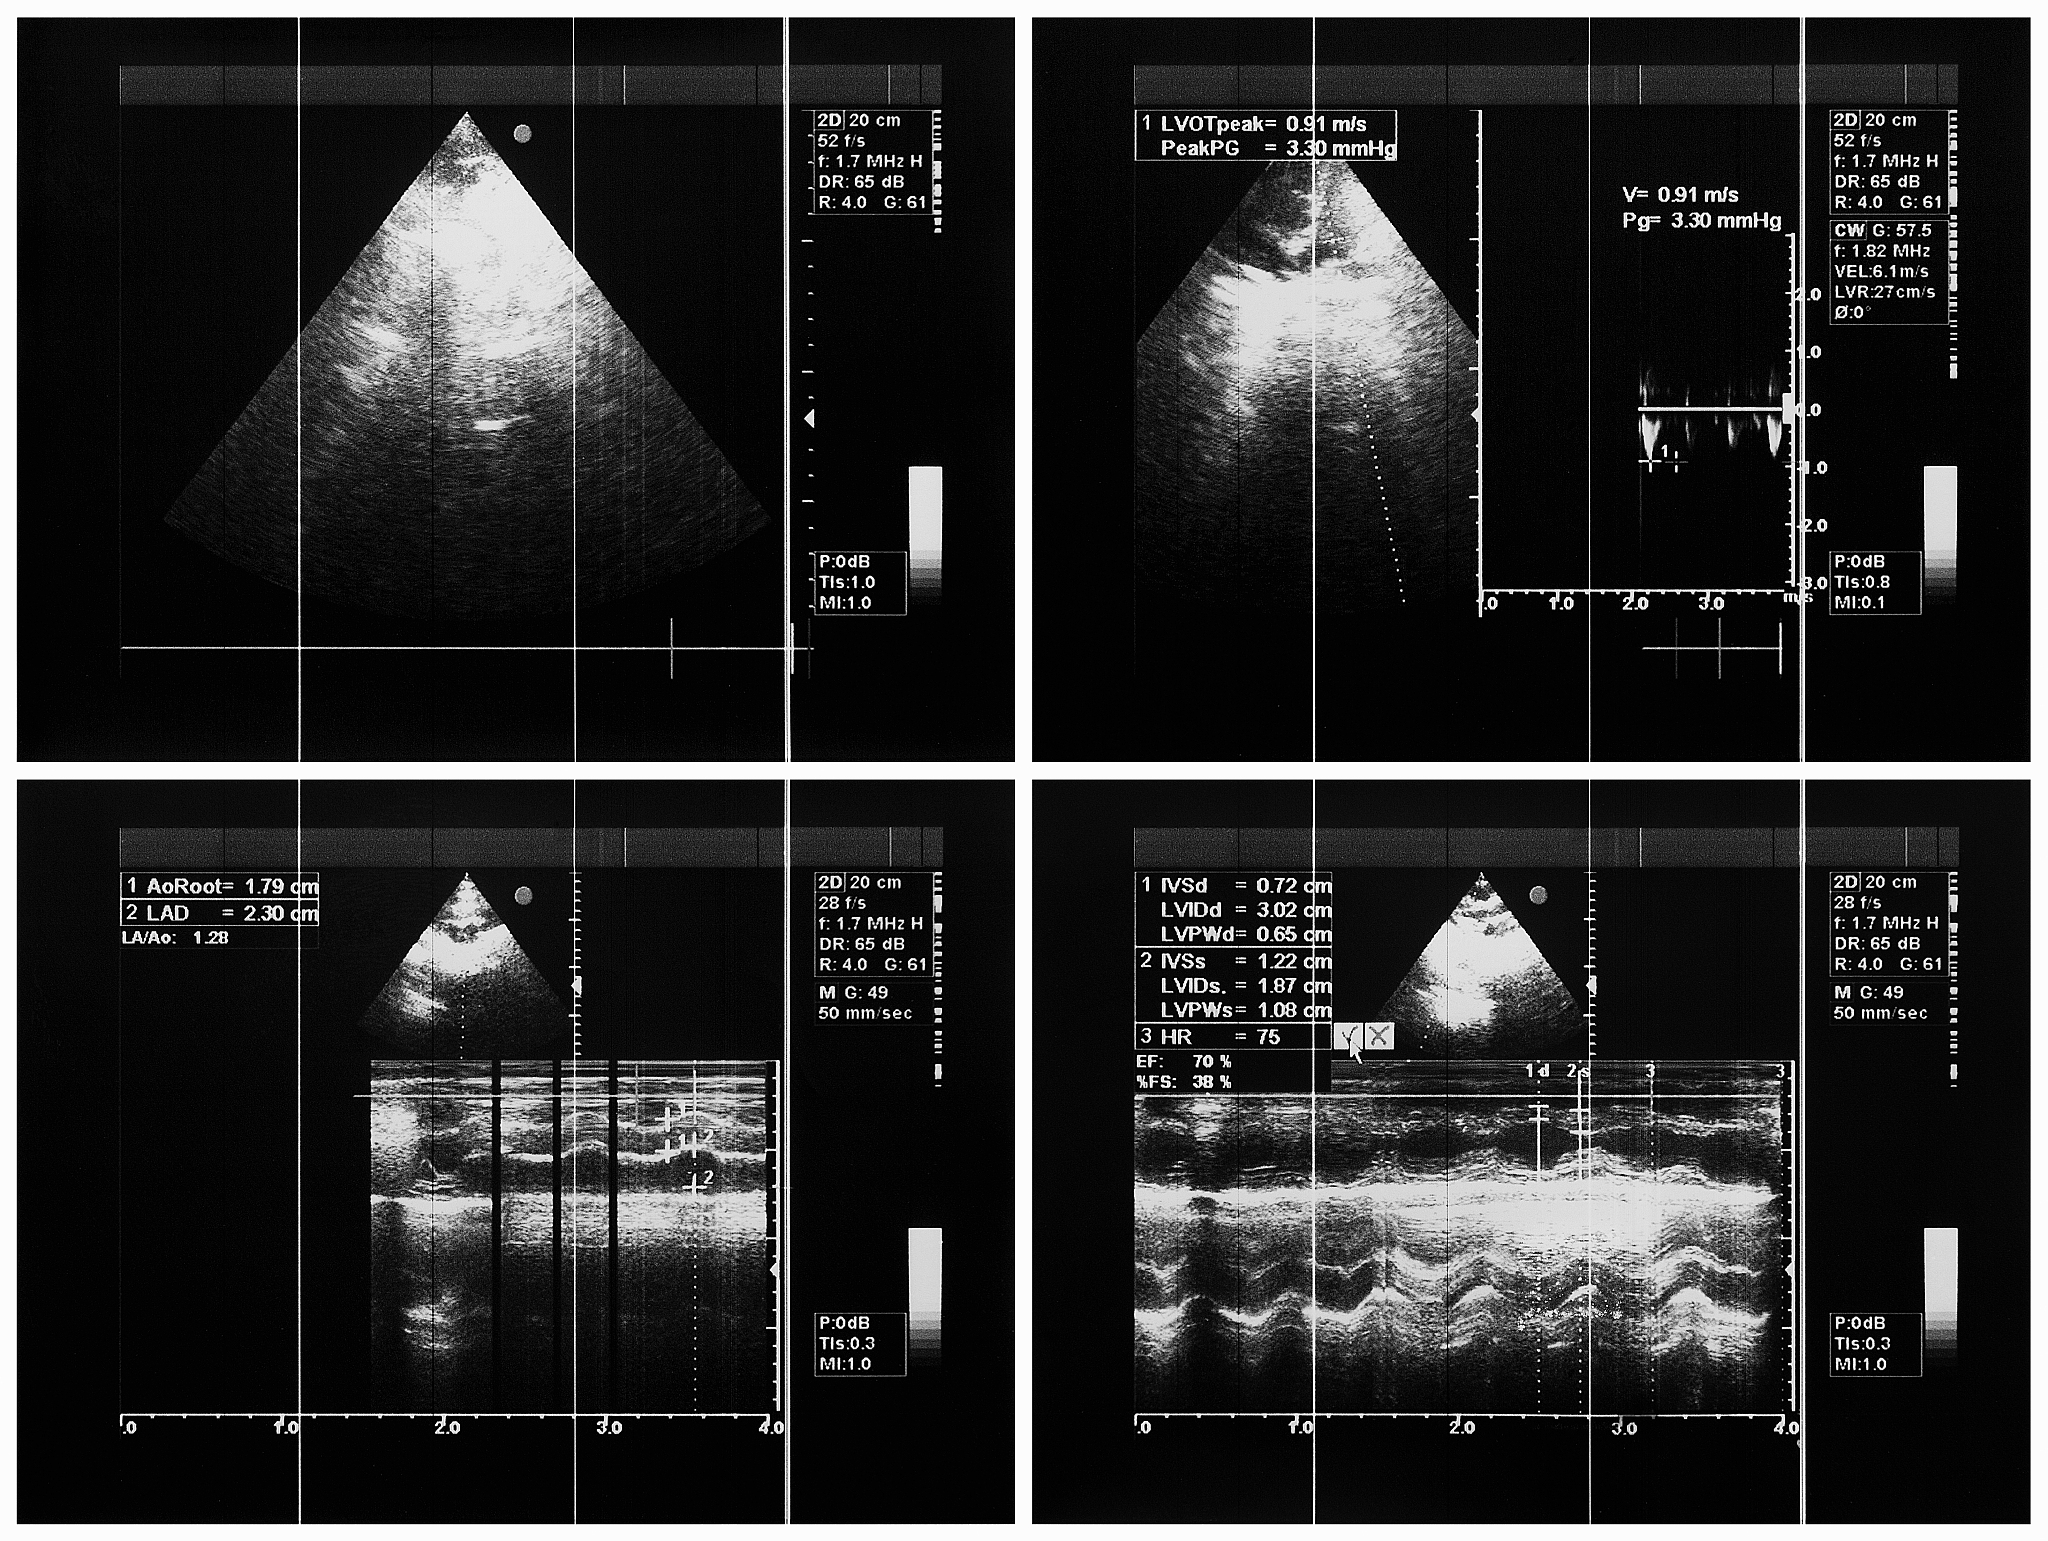

1. 室间隔缺损(VSD): 超声图像清晰显示室间隔上的缺损,可观察到血液从左心室流向右心室。2. 肺动脉狭窄(PS): 超声图像显示肺动脉瓣口狭窄,导致右心室血液流出受阻。多普勒超声可测量狭窄程度,为治疗提供参考。3. 主动脉骑跨(Overriding Aorta): 超声图像显示主动脉位于室间隔缺损上方,部分或全部骑跨在室间隔上。4. 右心室肥厚(RVH): 超声图像显示右心室壁增厚,这是由于右心室需要更强力地泵血以克服肺动脉狭窄带来的阻力。

超声心动图不仅可以帮助医生诊断法洛四联症,还能评估疾病的严重程度。通过观察心脏结构异常和血流动力学变化,医生可以制定个性化的治疗方案,例如手术修复或介入治疗等,以改善患者的预后。